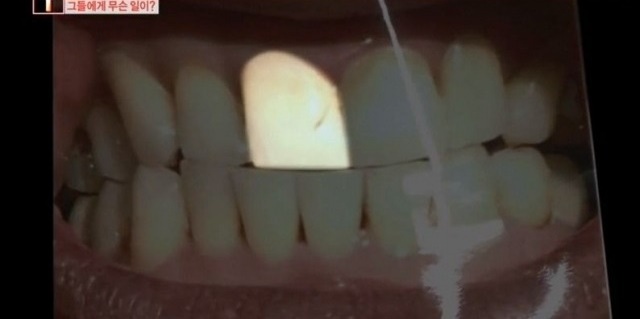

피해자는 “8월에 앞니 두 개를 레진 치료라고 해서 치아의 자국을 지우러 갔다”고 밝혔다.

그는 치아에 생긴 얼룩만 지우고 싶었는데 치과의 원장은 윗니에 충치가 조금씩 있다며 잇몸마취 상태로 윗니 10개를 마음대로 갈아버렸다고 한다.

피해자의 치아 상태를 살펴본 다른 치과 전문의는 “충치가 확실하지 않고 충치가 없었다고 보이는데 (윗니를) 많이 갈아버린 것”이라며 “(의사가 한) 행위 자체로만 보면 상해다”라고 목소리를 높였다.